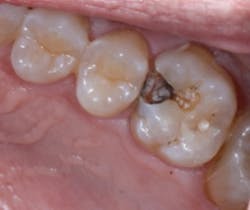

Figure 2 Occlusal view of Maxillary Right First Molar showing the amalgam and composite restorations. The margins appear intact around the amalgam The Canary System, using PTR-LUM energy conversion technology, is able to examine the restoration margin and detect caries along this interface earlier than would be detected with radiographs. Rapid, safe pulses of laser light combining infrared and luminescence allow one to examine lesions as small as 50 microns and subsurface caries up to 5 mm below the tooth surface or along the margin of composites and amalgams.

Figure 3 Bitewing Radiograph taken 4 weeks before the restoration was replaced. No sign of caries beneath the restorations on the maxillary first molar At our recall examination, we were concerned about the grey colouration around the amalgam on the mesial surface of the maxillary first molar. A bitewing radiograph did not reveal any sign of caries around the amalgam restoration and composite resin restoration in the mesial pit was not well delineated in the radiograph. A Canary Scan of the amalgam indicated caries along the buccal and distal margins of the restoration.